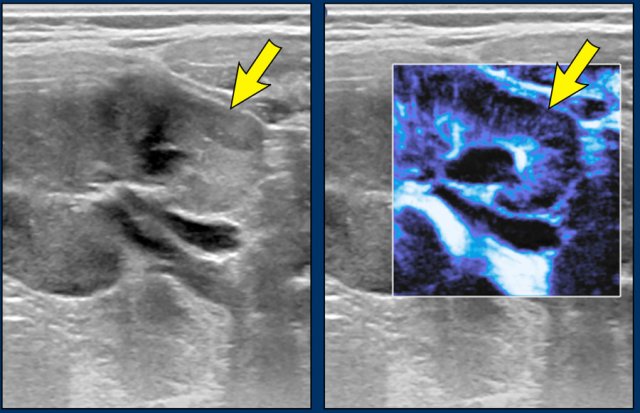

Image

Persistent nephroblastomatosis in a seven-year-old boy who was treated five years ago for a Wilms tumor. A peripheral rim of echogenic tissue is seen. These residual lesions are followed up with regular ultrasound untill 5 years after treatment.

Microflow imaging can help to identify hypoperfused areas with nephroblastomatosis.

Images

A two-year-old boy with a Wilms tumor in the left kidney and bilateral nephroblastomatosis. With microflow color imaging it is less perfused than normal renal tissue.

Continue with the MR images...

On MRI nephroblastomatosis is best seen on the post contrast images and diffusion-weighted images.

MRI images of the same patient show the hypoperfusion of the pathologic tissue and the strong diffusion restriction with low ADC values.

Patient was treated with pre-operative chemotherapy after which the tumor on the left side was resected through partial nephrectomy. The diffuse nephroblastomatosis was treated with monthly gift of AV (Actinmycin D and Vincristin) chemotherapy for one year.